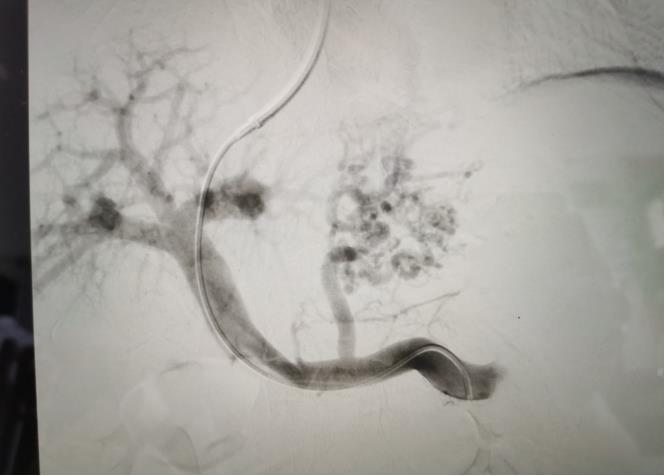

經(jīng)過我院血管介入科醫(yī)療團(tuán)隊的精心準(zhǔn)備,患者在數(shù)字減影血管造影機(jī)(DSA)導(dǎo)引下,順利經(jīng)頸靜脈入路進(jìn)入下腔靜脈并成功穿刺了門靜脈右支主干,術(shù)中栓塞了曲張的胃冠狀靜脈-食管靜脈叢將支架植入肝實(shí)質(zhì)內(nèi),支架兩端分別置于門靜脈和肝靜脈內(nèi),術(shù)程歷時2小時,術(shù)中患者時刻保持清醒,手術(shù)切口僅5毫米,術(shù)后第2天恢復(fù)飲食,腹脹、腹水癥狀明顯好轉(zhuǎn),未出現(xiàn)嘔血、黑便及肝性腦病等并發(fā)癥,術(shù)后第3天康復(fù)出院。